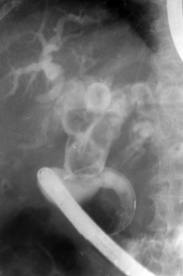

Болезнь которая образуется после полного или неполного удаления желчного пузыря, из-за неустранения патологических факторов оставшихся незамеченными во время операции (камни, кисты в желчных протоках) или вследствие повреждений желчных путей (рубцы). Приводит к нарушениям печени и пищеварения.